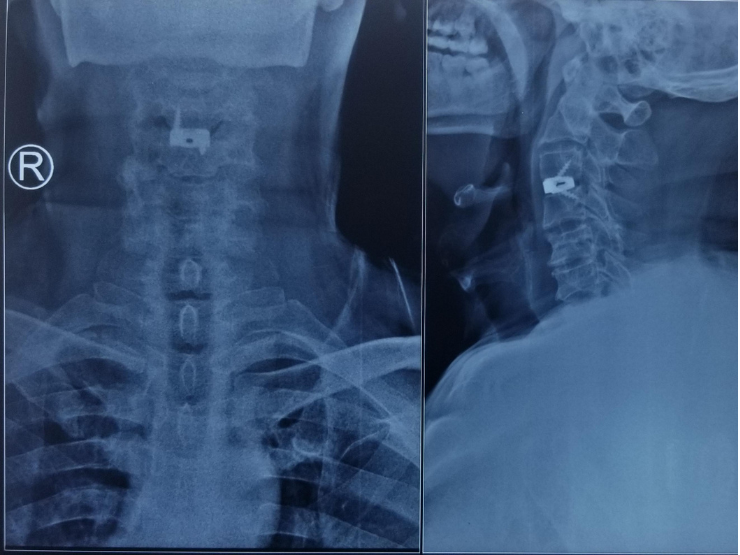

A case of Traumatic C4-5 Bilateral facet dislocation successfully managed with Anterior cervical spine surgery.

This 43 years old male patient presented with cervical spine fracture following history of trauma. He had weakness in his upper limbs and . . . .